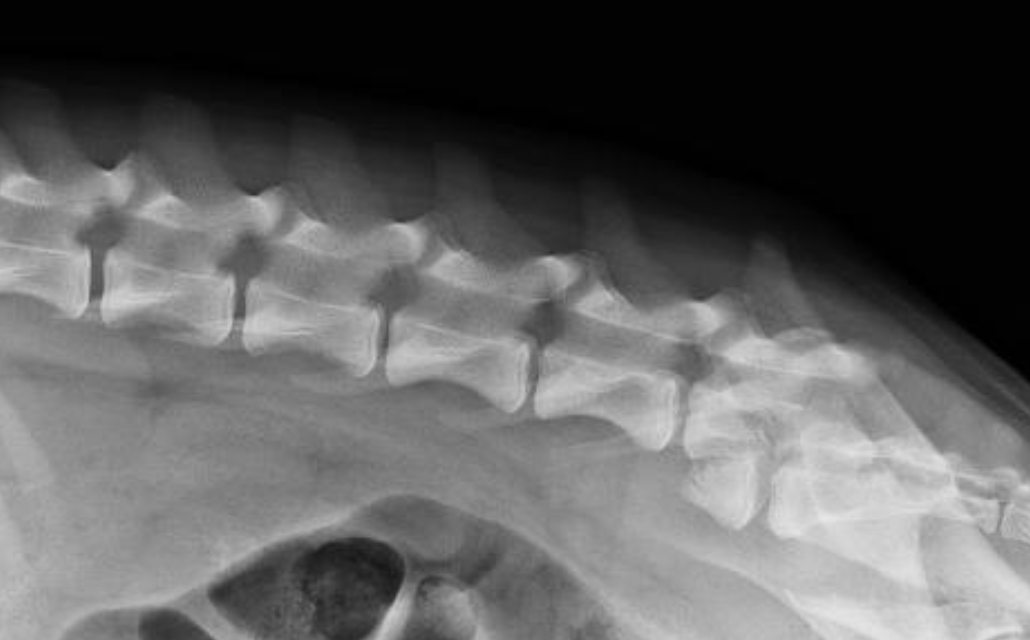

What are the characteristics of radiographs as a diagnostic for spinal trauma?

A

-thoracic rads, survey rads, and spinal rads typically performed

-lateral views okay to perform

-VD view should be taken with horizontal beam; do NOT place patient on back

-fairly good sensitivity at recognizing subluxations and fractures

-okay sensitivity at detecting fragments in spinal canal (compared to CT)

-avoid sedation if possible; can cause relaxation and instability of fractures